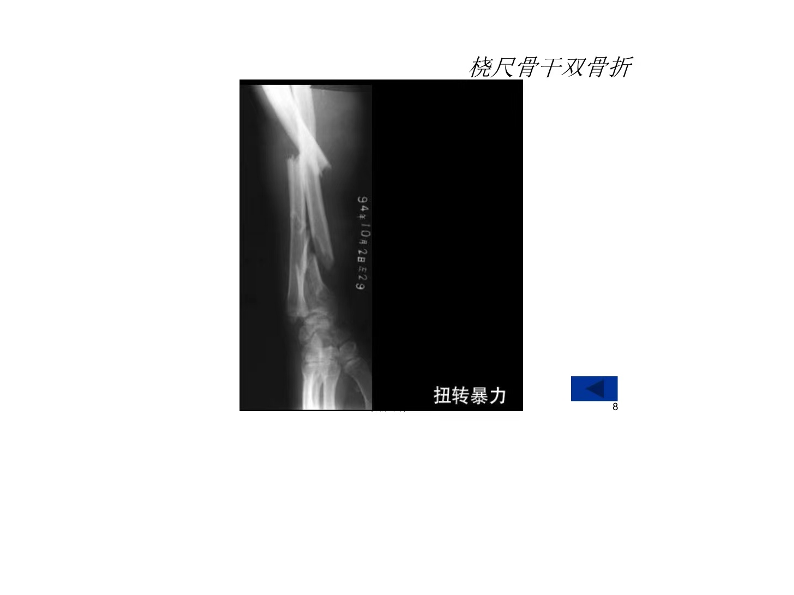

桡尺骨骨折